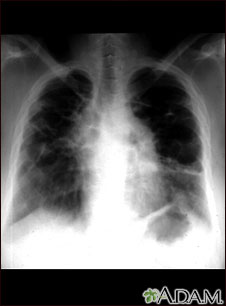

This film shows advanced sarcoid, scarring of the lungs (the light streaking), and cavity formation (the dark areas in the upper right side of the picture).